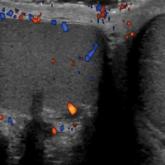

Emergency Imaging: Severe Left Testicular Swelling

- Author:

- Jessica Rotman, MD

- Keith D. Hentel, MD, MS

A 32-year-old man presented to the ED with acute onset of left testicular swelling and pain...